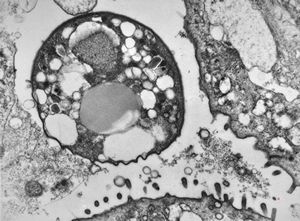

Giardia (Lamblia) intestinalis